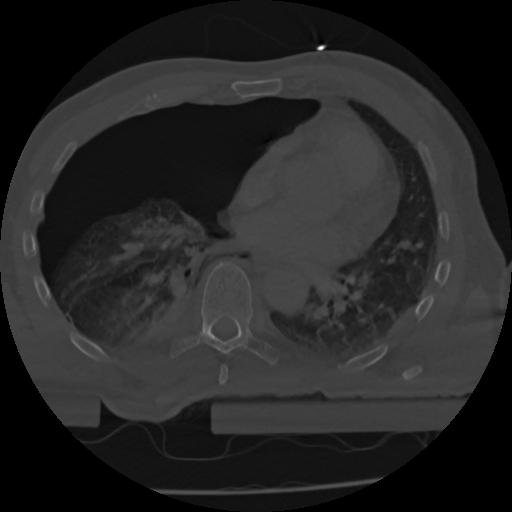

22 ANGIO,CE,Vol,0.5,ANGIO,,